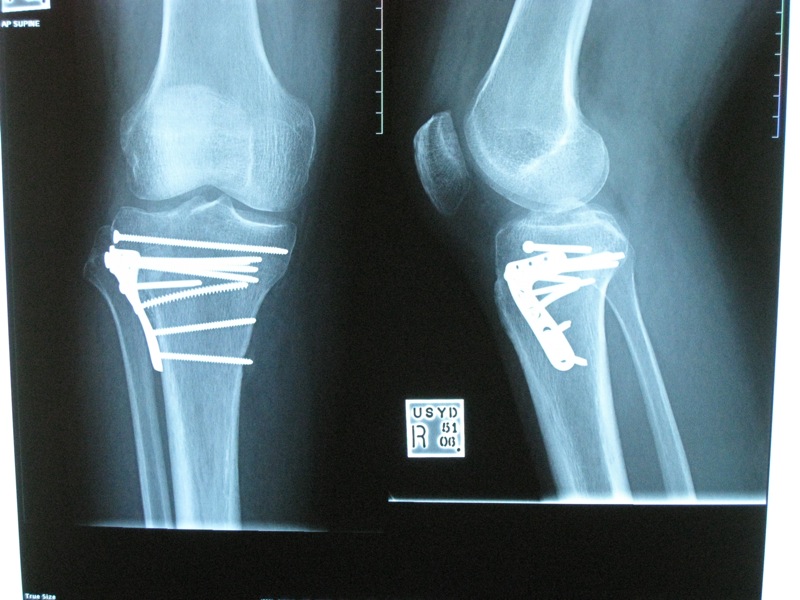

Took some more Xrays of the leg last week.

Lets just say that somebody was trigger happy on the old electric screwdriver :roll:

Crikey - you've got more hardware than Bunnings !!! :shock: Hope it works out OK, Fred. ;)

CRIKEY! Thats alot of hardware!!

Ol' mate could have at least put them all in straight :shock: I'm sure the M6 Fine x 25mm screw is crooked, and may well be cross-threaded too :D

geez that it some serious home improvement do it your self type hardware